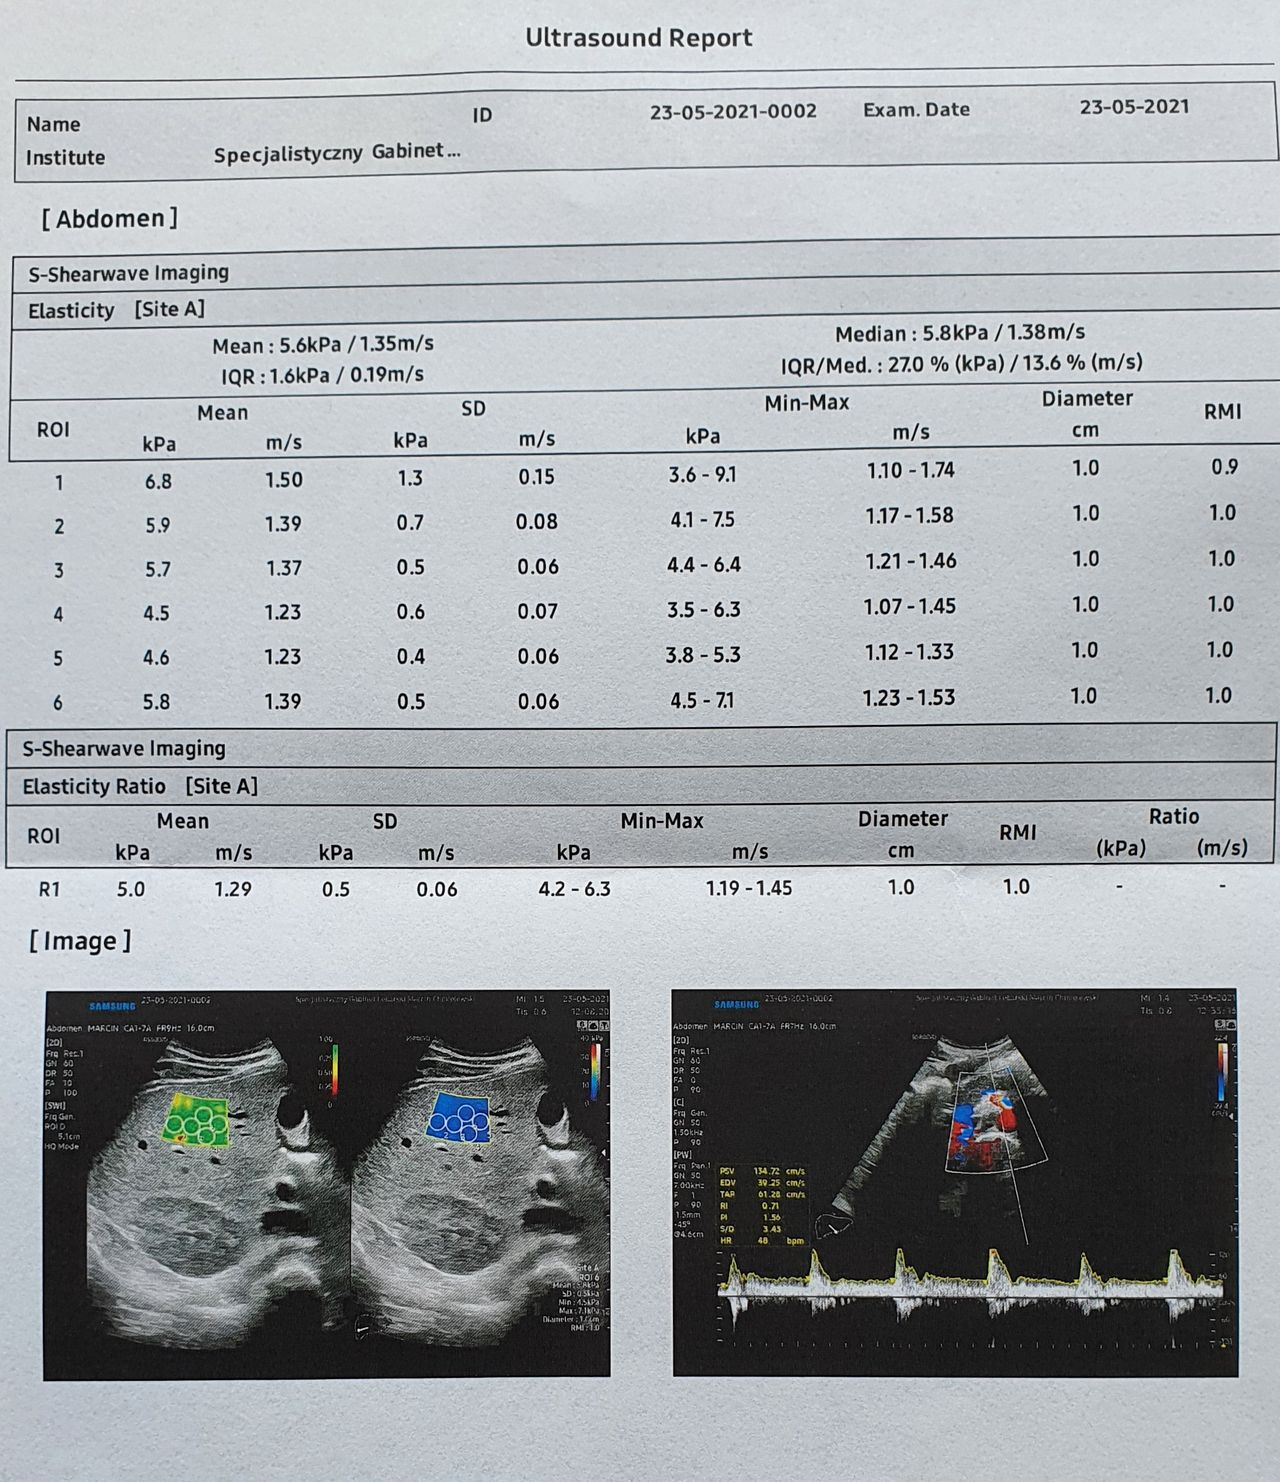

Elastografia wątroby Od 300 zł